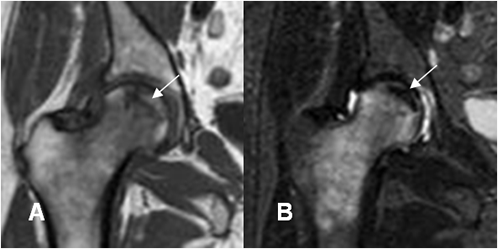

La ausencia de alteraciones subcondrales de baja señal o líneas hipointensas epifisiarias paralelas a la superficie condral, corresponde siempre a osteoporosis transitoria. (39, 40). (Fig 89).

Fig 89. Osteonecrosis.

A: RM coronal en T1 y B: RM coronal en STIR. Edema trabecular en la cabeza femoral, hipointensa en T1 e hiperintensa en STIR. Hay imagen subcondral hipointensa y paralela a la superficie condral en ambas secuencias, por osteonecrosis.